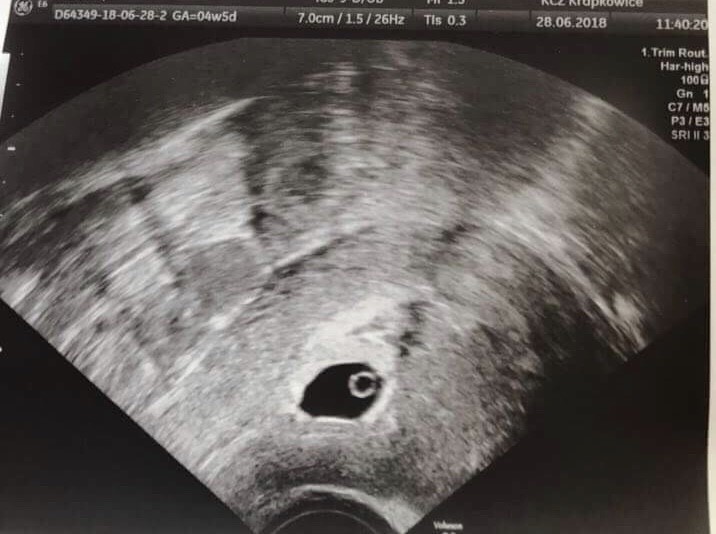

dzeikuje kochana, ciesze sie,ze znalazłam takie forum, bo idzie zwariowac. Widzisz tam cielko zolte? bo ja nawet nie wiem co to i gdzie tego szukac :( a lekarka jakos malo precyzyjna :( albo bala sie mi mowic. Myslisz,ze mam jakies szanse :(?

Tu jest pecherzyk z cialkiem bez zarodka...nie zamartwiaj sie..i nie czytaj...mij lekarz mi odrazu powiedzial by nie czytac internetow...musimy czekac

Załączniki

• 20190806_120720.jpg

20190806_120720.jpg

1,2 MB · Wyświetleń: 926